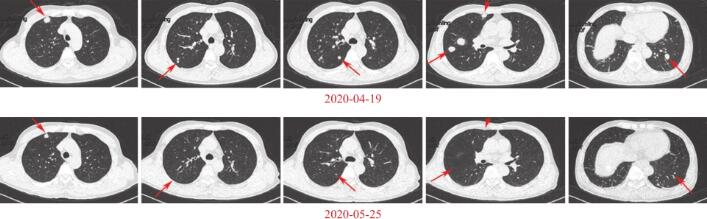

疗效评价:因仅行1个周期治疗,根据血AFP结果(61220.6μg/L,较前降低)及第2次入院前肺部CT平扫筛查结果,与前次比较示肿瘤部分消退:肝右叶病灶较前缩小(图1),双肺转移灶较前大部减小(图2),临床疗效为PR。

图2 多个肺部病灶缩小

2.胸部平扫(2020-04-19,本院)

双肺多发结节影,转移瘤可能,较大者直径约2.1cm。